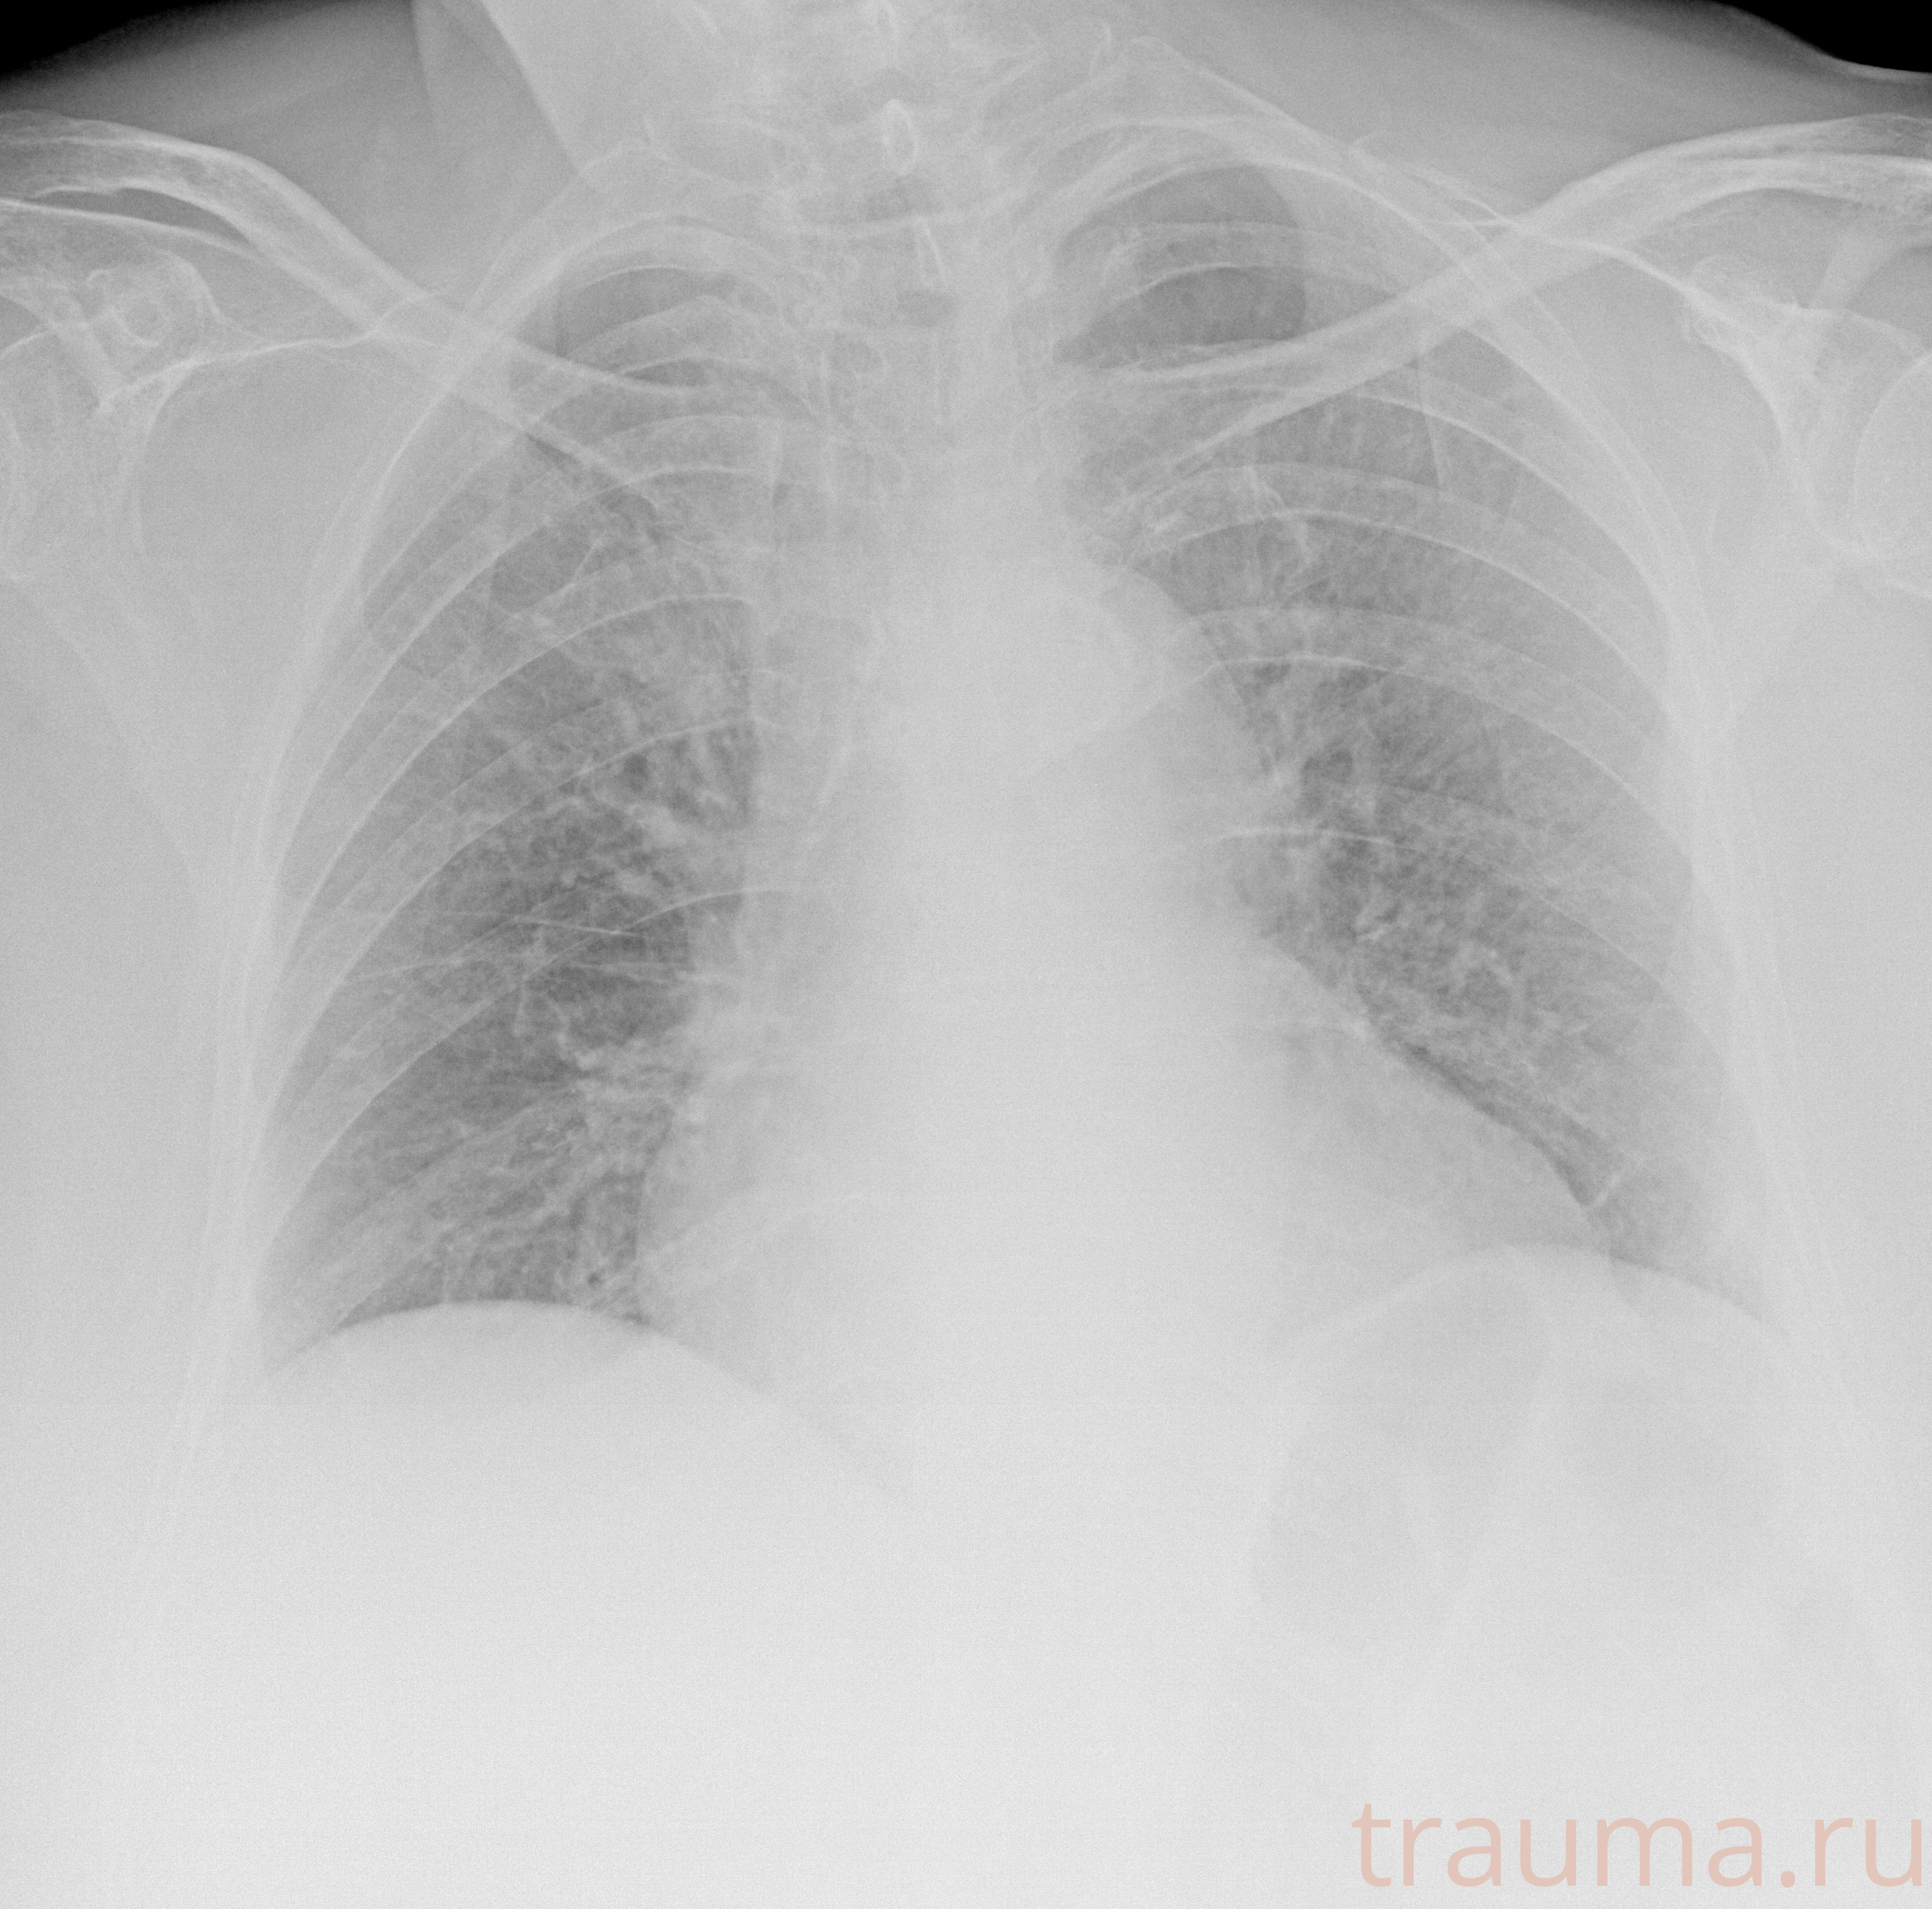

Рентген на дому: по вашему адресу приезжает врач-рентгенолог, травматолог-ортопед с мобильным рентгеновским аппаратом, проводит диагностику травмы или заболевания, делает необходимые рентгенограммы, дает рекомендации по дальнейшему лечению. Получить качественные снимки в домашних условиях возможно благодаря уникальной методике, разработанной МосРентген Центром для института  Склифосовского

при переломе шейки бедра и пневмонии от компании МосРентген Центр - партнера Института имени Склифосовского